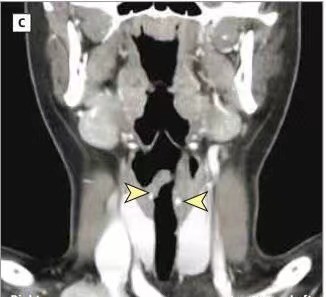

5.咽喉頭頸部腫瘤:

喉乳頭狀瘤、喉部血管瘤、喉癌、甲狀腺腫瘤等。